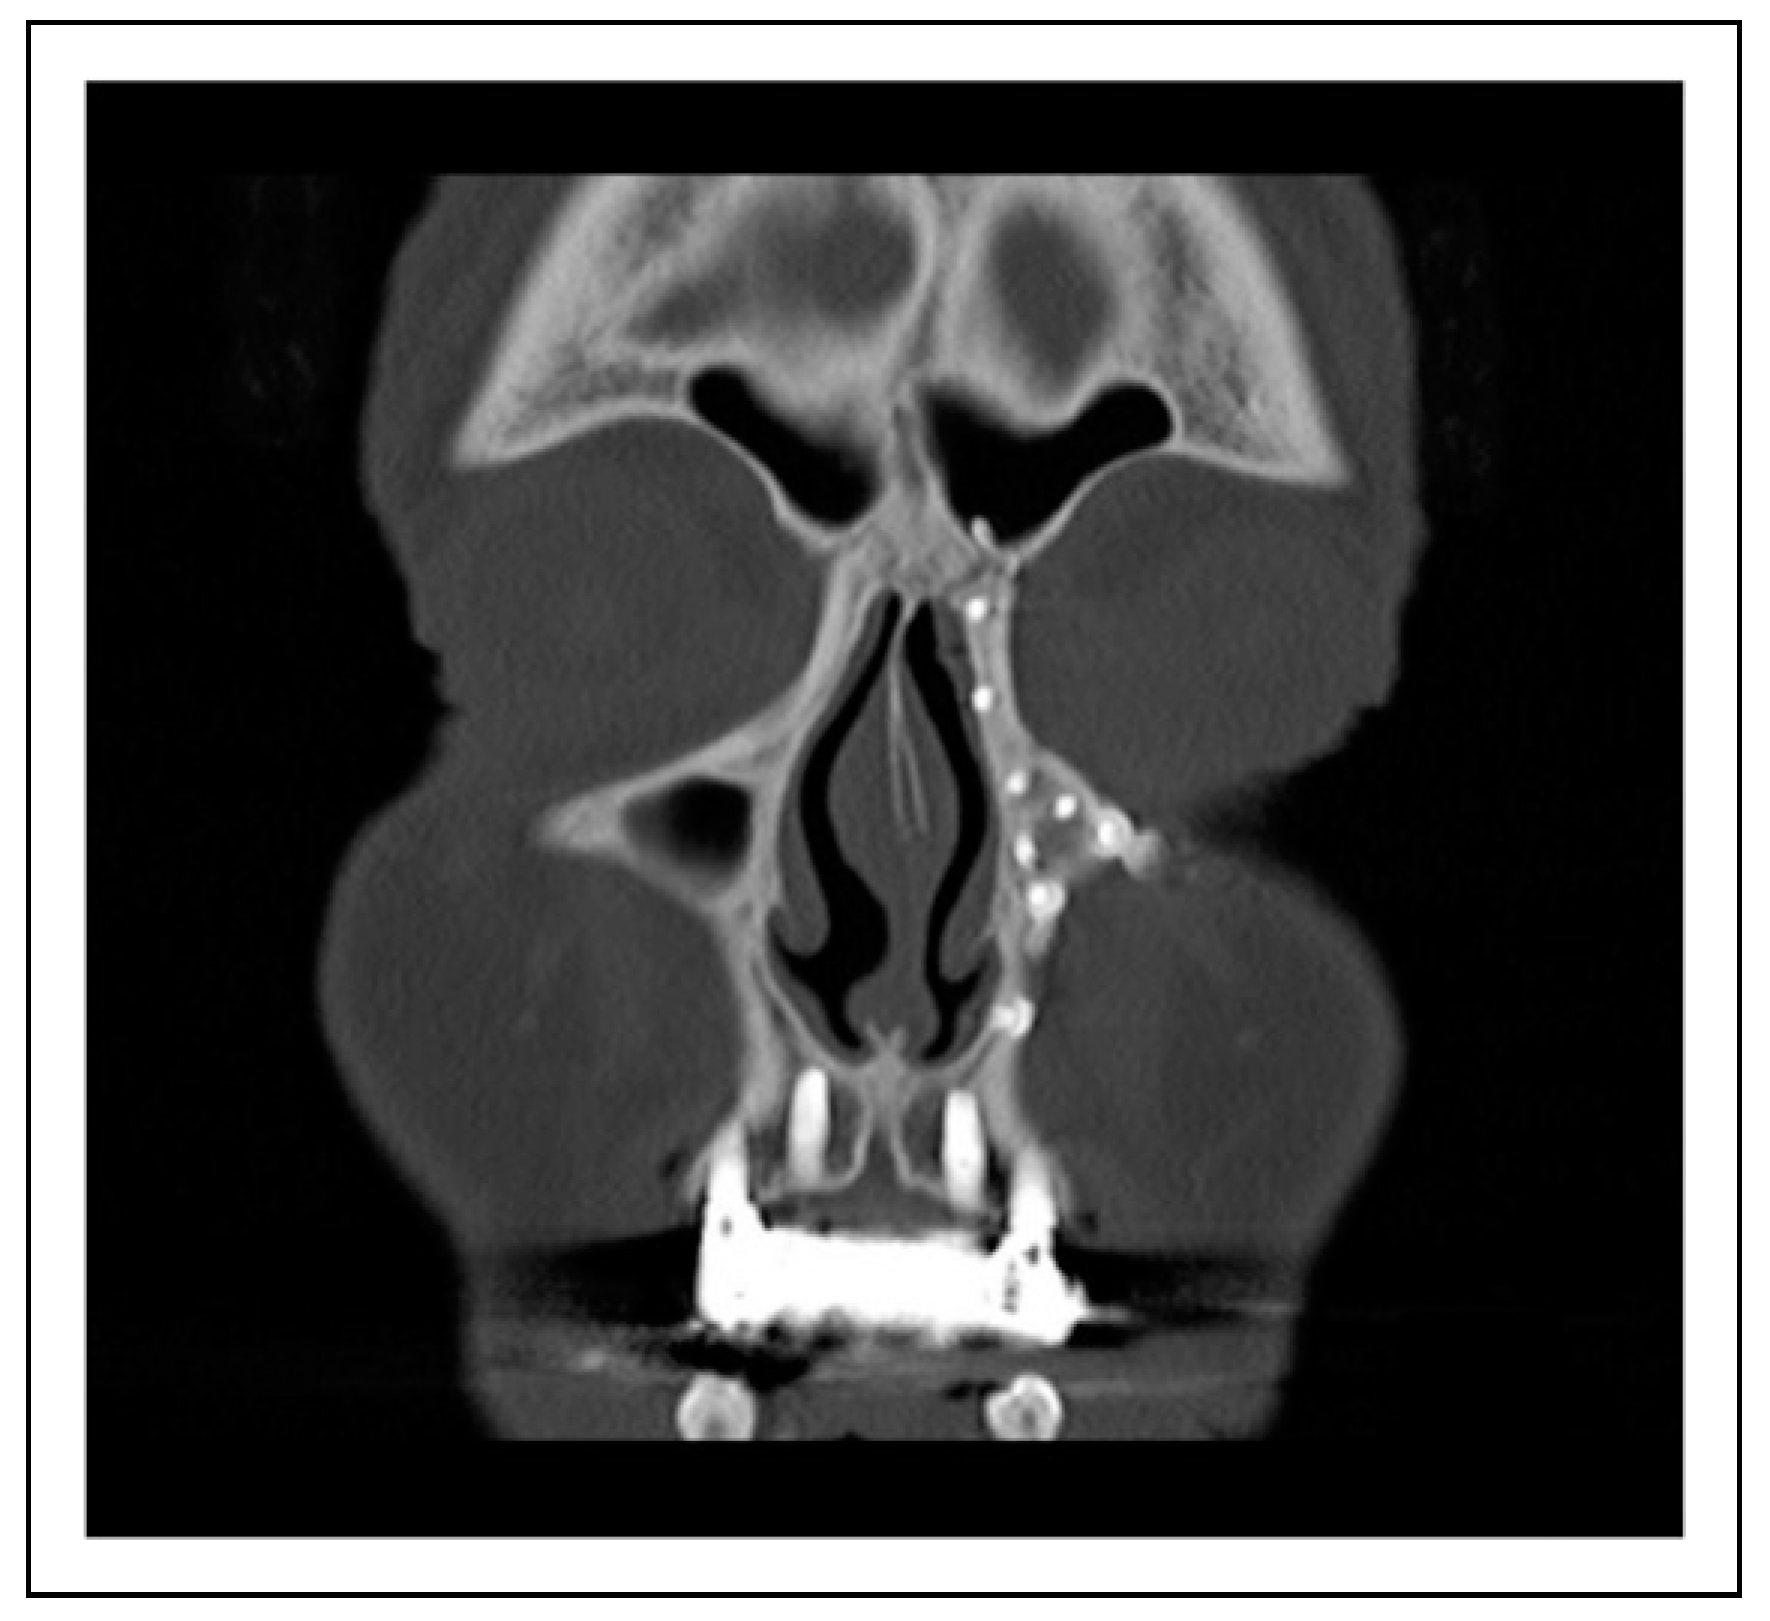

Case 1

Case 2